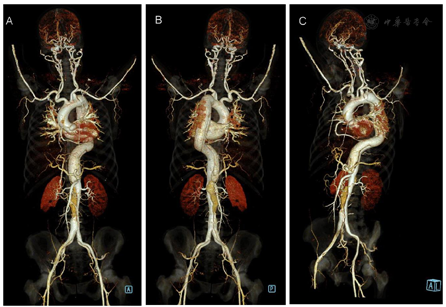

CTA图像显示:主动脉弓(近左锁骨下动脉根部)-右侧髂外动脉管腔呈双腔改变(图1A~C),破口位于主动脉弓降部(近左锁骨下动脉起始处),真腔小,假腔大,上至左锁骨下动脉根部,下至右侧髂外动脉末端。

三支头臂动脉顺序起源于主动脉弓,三支头臂动脉均起自真腔。